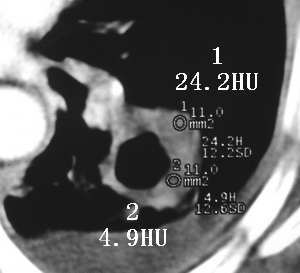

以下是引用sdqzwyx在2005-11-7 19:59:00的发言:[br]双肺弥漫大小不等的粟粒状结节影;肺纹理走行失去自然,粗细不均,边缘不规则,小叶间隔增厚;左上肺示不规则形致密影,从斑块边缘向周围伸出长短不一的致密索条影,临近的血管、支气管和叶间胸膜等结构受牵拉移位;左下肺示不规则团块状影,其内示空洞,洞内壁尚光整,左侧胸腔积液。右肺下叶背段亦示部分病灶融合。双肺可见局限性肺气肿。[br]诊断:结合病史符合三期矽肺表现(少数矽肺纤维斑块内可以形成空洞,一般认为是斑块中央感染引起坏死所致)但尘肺病人易合并肺结核,诊断可为三期+tb。所以此病人应进一步检查是否合并结核。